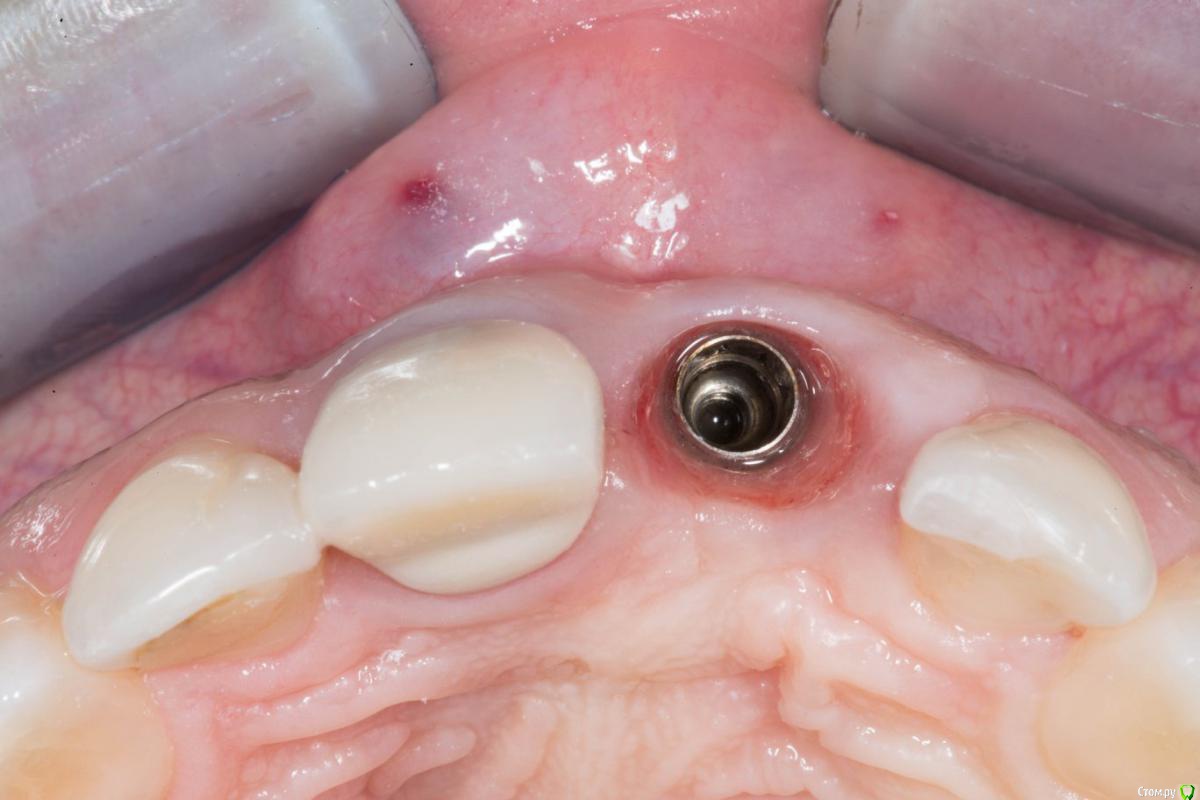

колесников Опубликовано 27 марта, 2018 Поделиться Опубликовано 27 марта, 2018 Так одно из другого выходит,разве нет? Нет винтовой фиксации -значит не верное позиционирование. По мне-так. Цемент,раскручивание тли перелом винта-это уже дополнительные бонусы. Про АД не скажу ,я его косяков не видел (кто-нибудь вообще видео?). С особенностями Нобеля знаком,от этой системы давно отказался, именно из-за особенностей и с АД по этому поводу несколько раз сцеплялся,но каждый остался при своём. Вот свежий случай. Сторонне работа,около 10 лет. Кстати Нобель,но тут не в этом дело. Видно что изначально Имплант поставлены по направлению гребня (где кость была),ортопед угловым все вывел. Итог налицо. Скажете :тут по другому никак,такой гребень. Сейчас работаю в первом секторе,гребень аналогичный,удалось выйти на винтовую и даже с нагрузкой. Ссылка на комментарий

колесников Опубликовано 27 марта, 2018 Поделиться Опубликовано 27 марта, 2018 (изменено) Вот ещё случай (из интернета). Тут ситуация не однозначная,с одной стороны абатмент изначально из диоксида циркония,а с другой это похоже штрауман тл . завтра скину свой случай,у меня мис стоит стандартный абатмент и коронка с розовой десной. Суть примерно такая же. Вестибулярное положение платформы из-за угла положения импланта,лизис компактной пластинки и прогнозируемо рецессия. Видно,что закрывать массированно мягкими тканями не резон,будет шишка. Надо смещаться коронально,но придётся менять форму абатмента и коронки чтобы было где расположится прикреплённой слизистой. Так вот,на платформенном соединении это практически не возможно сделать ,угроза переточить стенку абатмента и получить перелом. Проще переустановить Имплант в другом положении. Но иногда это практически не возможно Изменено 27 марта, 2018 пользователем колесников Ссылка на комментарий